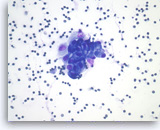

Non-Hodgkin B-cell lymphoma,

Pancreas FNA, Direct Smear.

The aspirates show dispersed single intermediate to large atypical lymphocytes.

20X

Non-Hodgkin B-cell lymphoma,

Pancreas FNA, Direct Smear.

The aspirates show dispersed single intermediate to large atypical lymphocytes.

20X

Non-Hodgkin B-cell lymphoma,

Pancreas FNA, Direct Smear.

At a higher magnification, the atypical lymphocytes show variations in size and shape. Scattered lymphoglandular bodies are seen in the background.

40X

Non-Hodgkin B-cell lymphoma,

Pancreas FNA, Direct Smear.

At a higher magnification, the atypical lymphocytes show variations in size and shape. Scattered lymphoglandular bodies are seen in the background.

40X